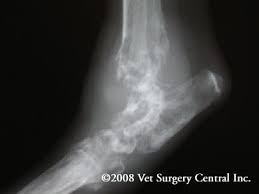

Cancer is not just one entity—it is any process of uncontrolled cell growth. There are three main forms of bone cancer, but the most common and aggressive is osteosarcoma, which accounts for up to 95% of all cancer diagnoses. Cancer in cats is the leading cause of death among cats. But i don't know that we have the answer for what causes most cancers in cats. Read on to learn 10 facts about cancer in cats. It is a tumor that often affects the long bones. There may also be some soft issue involvement. What you should know about osteosarcoma (bone cancer) in cats a type of bone cancer called osteosarcoma is the most common type of primary bone cancer, accounting for over 95% of all bone tumors.

Some tumors may grow slowly and do not typically spread, called benign, while others will act aggressively called malignant. We do know people are keeping cats longer. For every type of cell in the body, from your cat's skin to her stomach and blood vessels, there is a corresponding type of cancer. Limbs (upper arm and upper leg bones) pelvis (hipbones) rib cage. The connective tissue that is found between the bones and joints. Cats can get many different kinds of cancer, but the ones that most commonly affect kitties are lymphosarcoma, squamous cell carcinoma, and mammary (breast) cancer. For example, lymphoma affects the lymphatic system, while osteosarcoma affects bone. Osteosarcoma is also the most common bone tumor in cats, but the behavior of this tumor type is less aggressive than in dogs.

The rate of metastasis at the time of diagnosis is low.

This tumor typically occurs in the arm near the shoulder and in the leg near the knee in children, adolescents, and young adults but can occur in any bone, especially in older adults. The rate of metastasis at the time of diagnosis is low. It is seen more often in large breed cats. This cancer can lead to bone disintegration and may spread into the soft tissues surrounding the affected bone. A cat's mouth, similar to our own, is made up of several different cell types; It is a tumor that often affects the long bones. It is the most common oral cancer in cats. Squamous cell carcinoma is a highly aggressive form of oral cancer in cats, and it can be difficult to detect since felines are notoriously furtive about showing signs of illness. But i don't know that we have the answer for what causes most cancers in cats. Like humans, cancer in cats manifests as tumors. An oral tumor is an abnormal growth of cells. There are many types of cancer in cats. It is caused by uncontrolled cell growth, and affects a wide range of cell types and organs in the body.